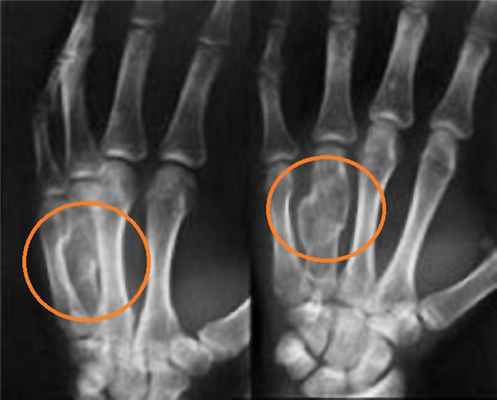

Большинство переломов дистального отдела лучевой диагностируются обычной рентгенографией в 2-х проекциях. Компьютерная томография (КТ) необходима при внутрисуставных переломах.

Для подтверждения диагноза выполняются рентгенограммы лучезапястного сустава в 2-х проекциях. Рентген являются наиболее распространенным и широко доступным диагностическим методом визуализации костей.